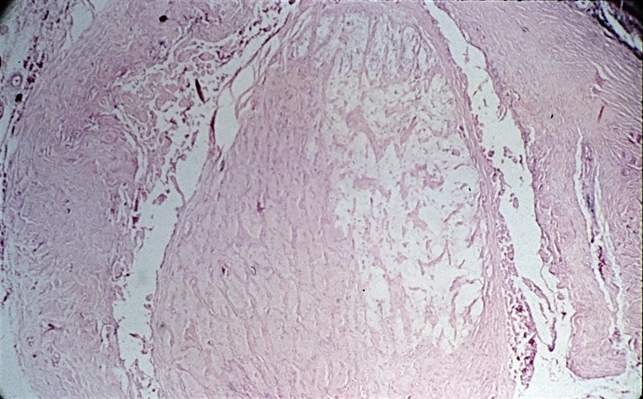

- sequelae, optic atrophy

- Sequelae. Cavernous degeneration of the optic nerve (Schnabel's cavernous atrophy) shows cystic spaces which appear clear in hematoxylin and eosin stained sections (H&E x21).